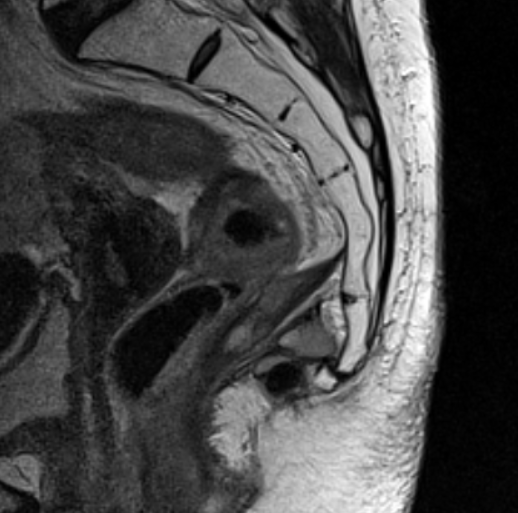

МРТ крестцово-копчикового отдела позвоночника

Магнитно-резонансная томография крестцово-копчикового отдела позвоночника – важный метод исследования, который позволяет оценить состояние крестца и копчика.